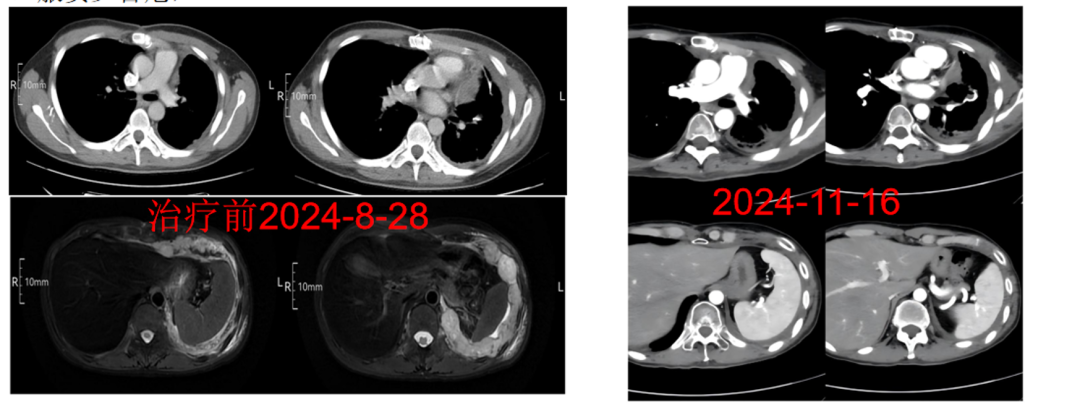

病例2:纵隔横纹肌肉瘤伴肺转移的大范围精准治疗

向先生(化名)在2024年8月确诊为纵隔横纹肌肉瘤,并伴有肺转移。在接受手术治疗和化疗后,针对肺转移瘤及胸膜病灶,他选择了TOMO放疗。

TOMO放疗的照射范围广泛,能够覆盖胸腔内的复杂病灶,实现多靶区同时照射,这对于处理向先生的病情非常有利。通过多叶光栅和螺旋CT扫描技术,TOMO放疗实现了对肿瘤的高精度调强照射,减少了对肺、心脏等敏感器官的损伤,提高了治疗效果。同时,其适应复杂解剖结构的能力,使得TOMO放疗能够处理形状不规则、位置复杂的胸膜病灶,确保治疗的安全性和有效性。

治疗前后对比图